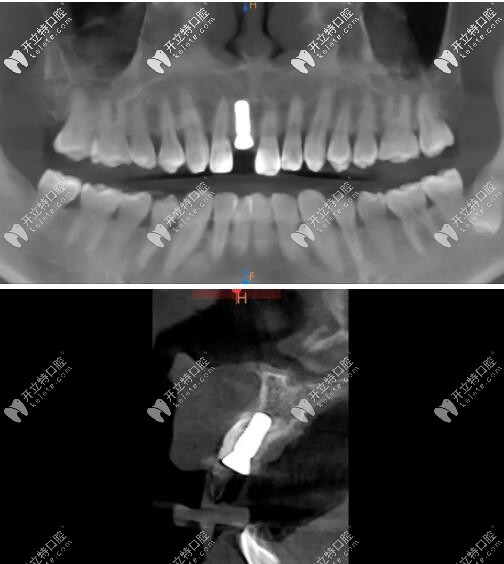

術(shù)后CBCT顯示植入正確的三維位置,種植體唇側(cè)骨量充足;

瑞士iti鈦親水BL 4.1mm*10mm種植體

X線顯示:臨時(shí)修復(fù)體就位良好;

X線片顯示就位良好;

瑞士iti親水BL種植體種植后x片